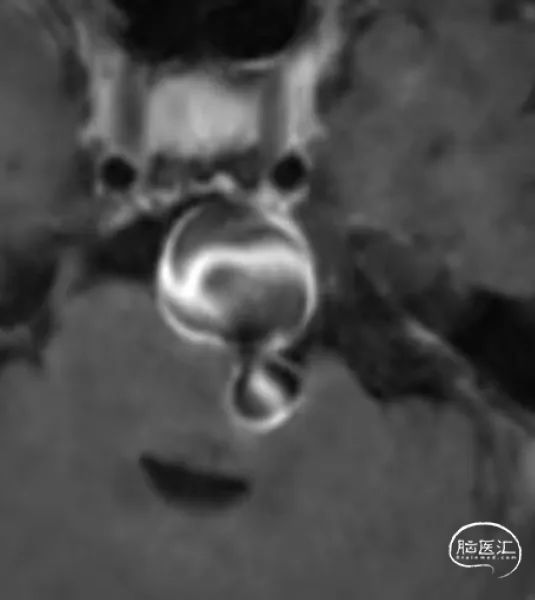

高分辨磁共振